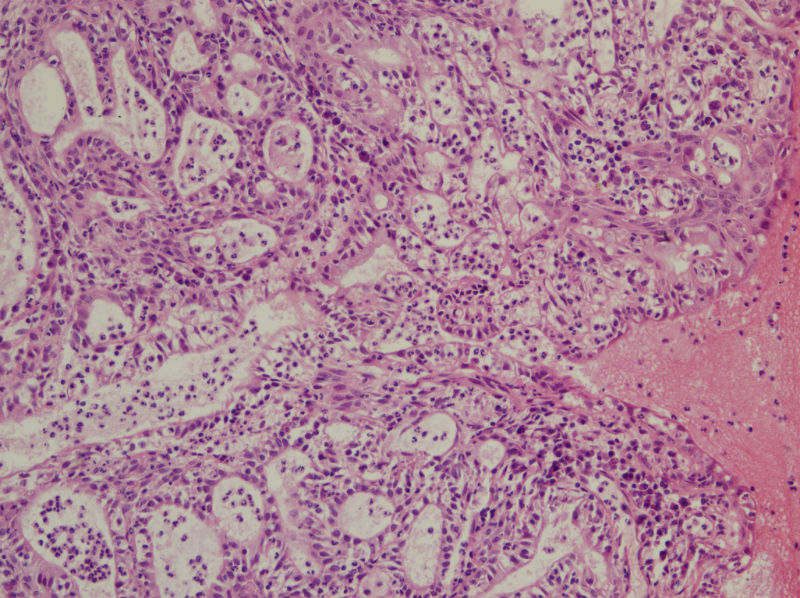

45岁,宫颈息肉?请老师指教

Benign endocervical polyp with SM and MGH. You do not need classify benign endocervical polyp because it has no impact on clinical management.

宫颈息肉伴腺体磷化

宫颈息肉伴糜烂,局部腺体及黏膜上皮鳞状上皮化生。至于说具体分型,与临床治疗和预后都没有关系,可以不分。

宫颈息肉伴鳞化和微腺体增生

宫颈息肉伴腺体的鳞化,我个人感觉息肉的分型比较复杂,有的地方存在宫颈腺体增生型,有些地方血管型,还有纤维型也可见。

宫颈息肉伴腺体鳞化,微腺体增生

宫颈及宫颈内膜息肉,腺体增生及鳞化,鳞化跟中药没有关系,跟炎症刺激有关系。

我想请问,息肉的分型.另外患者服用大量妇科中成药物和腺体的鳞化有关吗?

慢性炎,腺体有鳞化